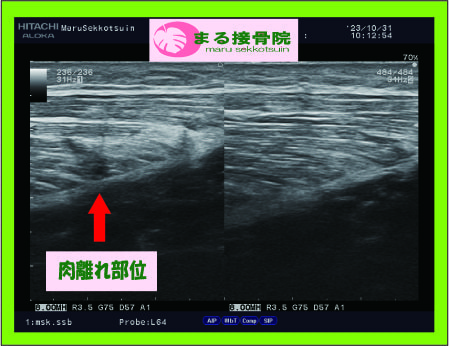

エコー画像、ふくらはぎの筋腹内に断裂部分(空洞部分)が診られ、特殊な撮影方法で出血度合も確認できます。

エコー検査は筋肉の状態を正確に確認でき、的確に治療をできます。